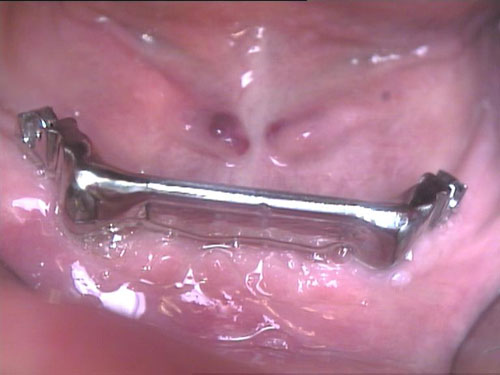

Brückenersatz